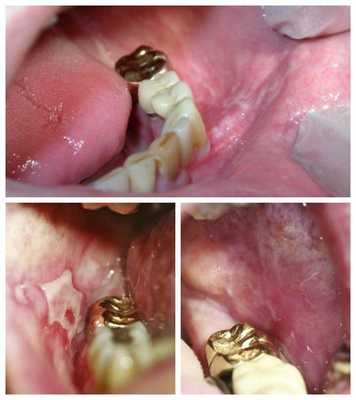

- На верхней челюсти стоит бюгельный протез, в области жевательных зубов нижней челюсти слева — мостовидный протез с опорами на 36 и 33 зубы с покрытием из нитрид титана (под золото).

- Удаление мостовидного протеза в области 33, 34, 35 и 36 зубов.

- Удаление пульпы 33 и 36 зубов с трёхмерным пломбированием корневых каналов с последующим изготовлением и фиксацией мостовидного протеза на основе диоксида циркония с опорой на 33 и 36 зубы.

После удаления мостовидного протеза с зубов 33 и 36, покрытого нитрид титаном, пациент отметил значительное уменьшение дискомфорта, жжения, кислого вкуса в ротовой полости. Через две недели после установки мостовидного протеза на основе диоксида циркония чувство жжения и покалывания языка исчезли совсем.